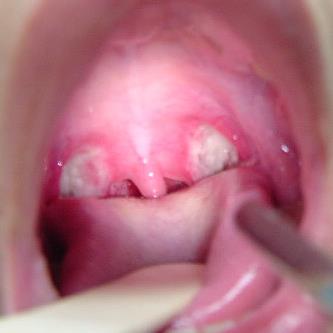

Symptoms of strep throat usually include: a sore throat that feels scratchy, difficulty or painful swallowing, red or swollen tonsils, white patches in the back of your throat, small red spots on the roof of your mouth, swollen lymph nodes in your neck, headache, fever, fatigue, rash, stomach ache and vomiting.

| Pus present on the tonsils (pus sometimes drains) | Extreme fatigue – early and prominent and lasting 2 weeks or more | Sneezing | Red, raw scratchy throat |

| Grey or white covering on the tonsils | Muscle and joint aches – usually severe | No symptoms of strep | |